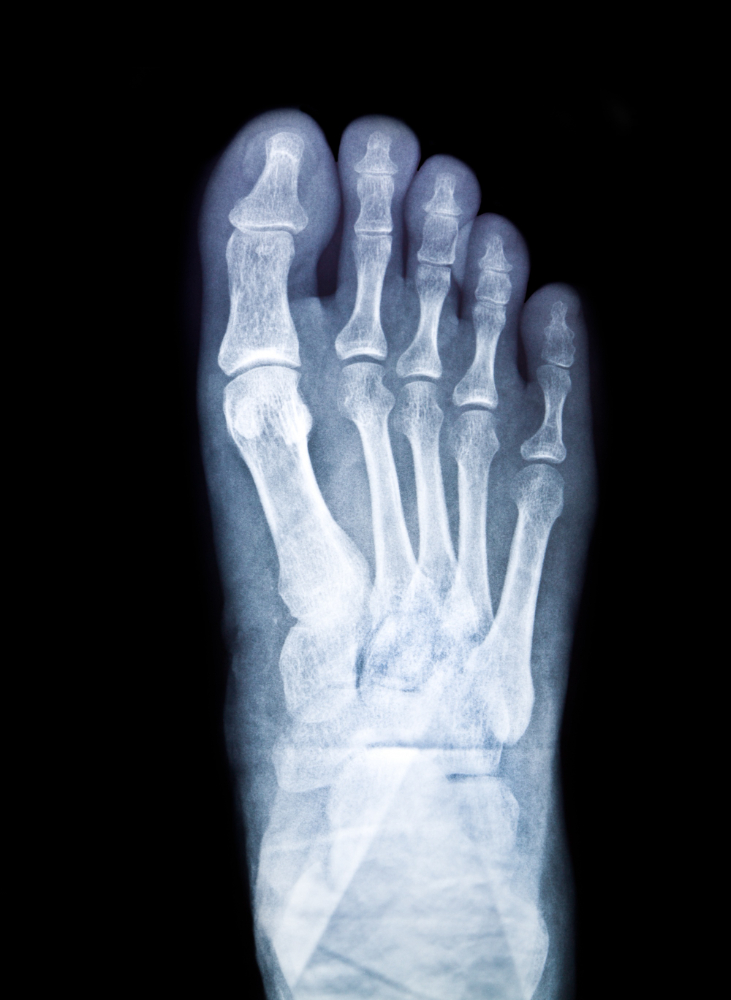

The X-Ray Little Finger AP/LAT test provides two standard views of the fifth finger: the Anteroposterior (AP) and Lateral (LAT). The AP view captures the front-to-back image of the finger, while the LAT view provides a side profile. Together, these views reveal small bone fractures, dislocations, or joint deformities.